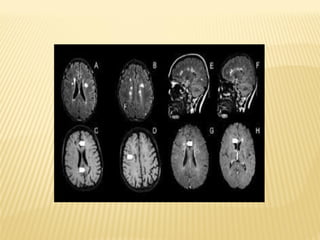

A esclerose múltipla é uma doença inflamatória crônica que

compromete o sistema nervoso central e atinge 2,5 milhões de

pessoas no mundo – sendo 30 mil no Brasil – em uma

proporção de três mulheres para cada homem. Segundo a

A doença afeta o sistema imunológico do corpo, que confunde

células saudáveis do próprio corpo com células “intrusas”, e as

ataca provocando lesões no cérebro. O sistema imune do

paciente ataca a bainha de mielina – capa de gordura que

envolve as ramificações dos neurônios com o objetivo de

protegê-los e facilitar a propagação de estímulos.